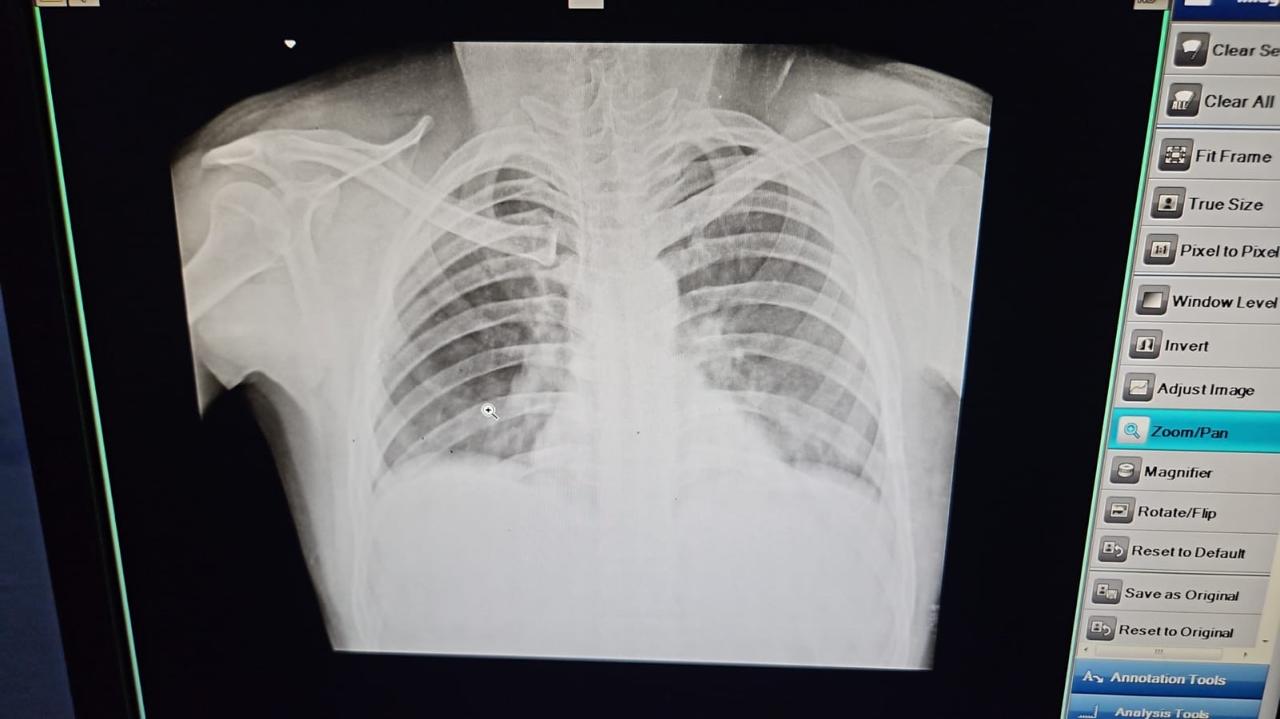

मुख्य चिकित्सा अधिकारी डॉ बी एस रावत द्वारा बताया गया.बृहस्पतिवार को उपजिला चिकित्सालय पुरोला में चिकित्सकों की सूझबूझ एवं कुशलता से एक गंभीर दुर्घटना में घायल मरीज का जीवन सुरक्षित किया गया.उनके द्वारा चिकित्सा दल में शामिल फिजिशियन डॉ मनोज असवाल, सर्जन डॉ अर्पित राय, डॉ माही, नर्सिंग ऑफिसर हर्षमणी नौडियाल, रेडियोग्राफर अनूप नौडियाल आदि की सराहना करते हुए बताया गया कि मनवीर सिंह ग्राम देवजानी की छाती में लकड़ी का टुकड़ा फँस गया था.

घटना की गंभीरता को देखते हुए चिकित्सकों की टीम ने तत्परता से ऑपरेशन कर लकड़ी का टुकड़ा सफलतापूर्वक बाहर निकाला गया. यह शल्यक्रिया अत्यंत जोखिमपूर्ण थी.परंतु चिकित्सकों की विशेषज्ञता एवं टीमवर्क से मरीज को सुरक्षित बचा लिया गया।